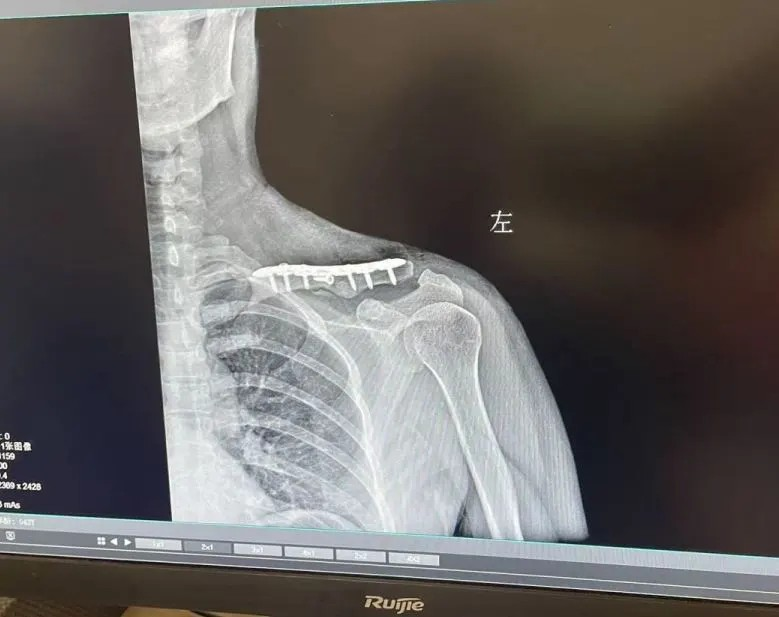

在(zai)一(yi)箇(ge)咊(he)往常一(yi)樣的(de)平凡的(de)工(gong)作(zuò)日(ri),沒想到(dao)接下來一(yi)場(chang)意外正向小(xiǎo)麗(化名(míng))悄然襲來。 宜咊(he)的(de)員(yuan)工(gong)小(xiǎo)麗正在(zai)騎車(che)通(tong)勤的(de)路上,忽然一(yi)輛電(dian)動(dòng)車(che)沖了(le)過(guo)來,撞到(dao)了(le)她,車(che)身失衡的(de)瞬間,小(xiǎo)麗重(zhong)重(zhong)摔